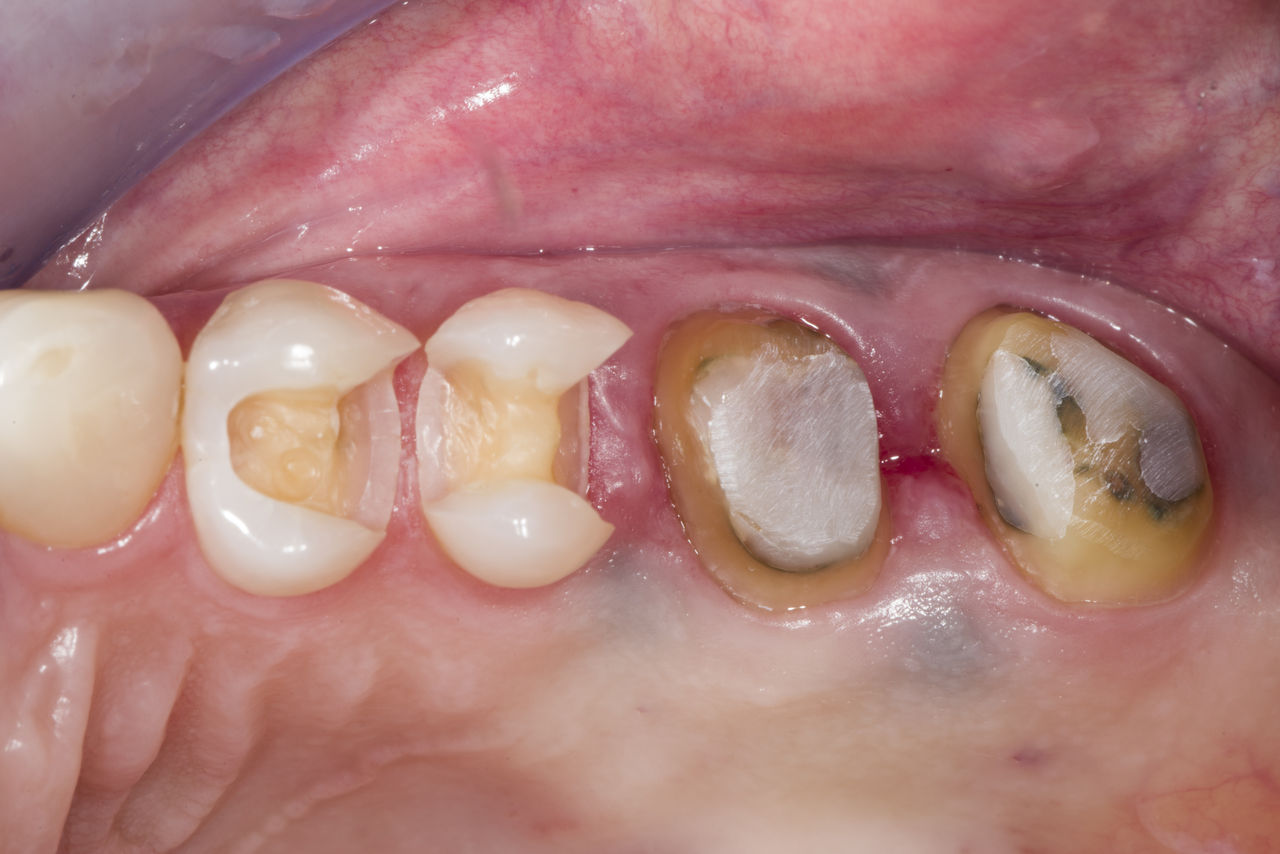

Before

Fractured metal-ceramic crown on tooth 14, which had previously been treated endodontically.

After

Translucent full zirconia crown for an esthetic result with maximum resistance and retention shape.